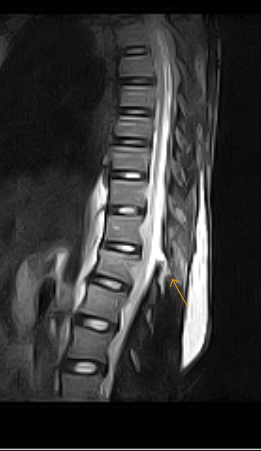

These are MRI images of 19year old after fall. MRI images show only minimal wedging of the marked vertebral body along with disruption of the interspinous ligaments posteriorly and ligamentum flava. The concept of three columns of support in the thoracic and lumbar spine is well accepted. The anterior column consists of the anterior vertebral body, the anterior longitudinal ligament, and the anterior annulus fibrosus. The middle column comprises the posterior vertebral body, the posterior longitudinal ligament, and the posterior annulus fibrosus. Hyperextension can result in injury to the anterior column or to both the anterior and middle columns. The posterior column consists of the posterior elements of the spine, ligamentum flavum, interspinous ligaments, supraspinous ligaments, and facet joint capsules. Hyperflexion may result in injury to the middle and posterior columns.